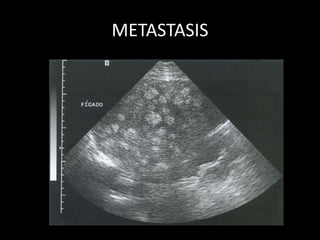

METÁSTASIS HEPATICAS

• Nódulos de distintas características, múltiples

METASTASIS